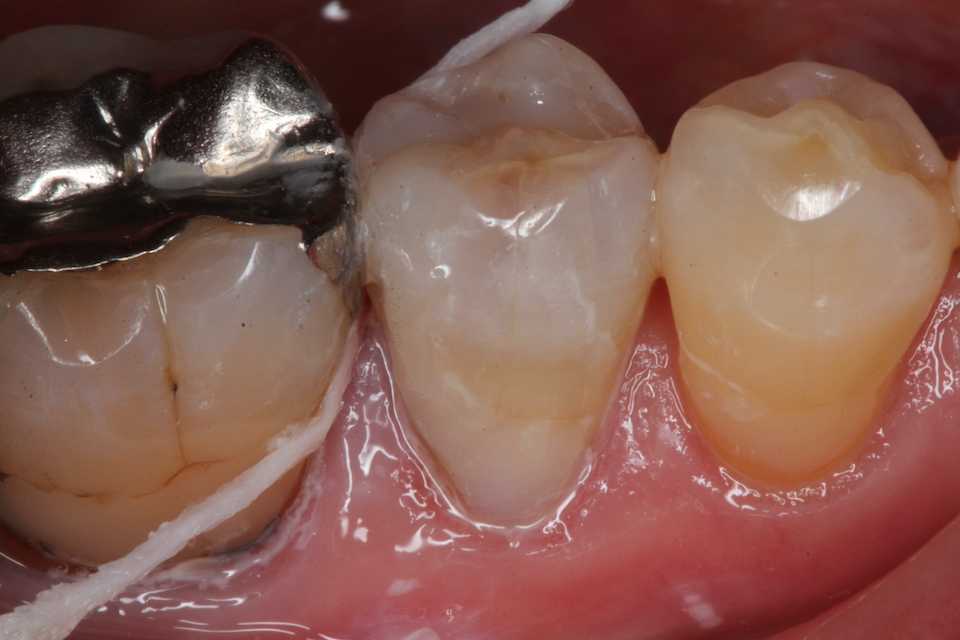

50代女性、右下5、インレー2次カリエス

ストリップスも使わないでも隣接面窩洞のCR充填は可能だ。

では時系列でどうぞ